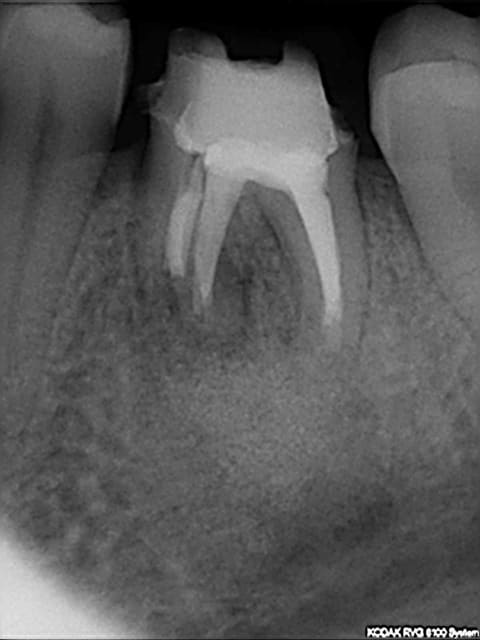

belle lésion péri apicale

je découvre ça à la pano, la 46 a été traitée en 1980 suite à une lésion endo paro, le patient ne se plaint de rien......je surveille ou j'interviens?

Il s'agit de la 36 non?